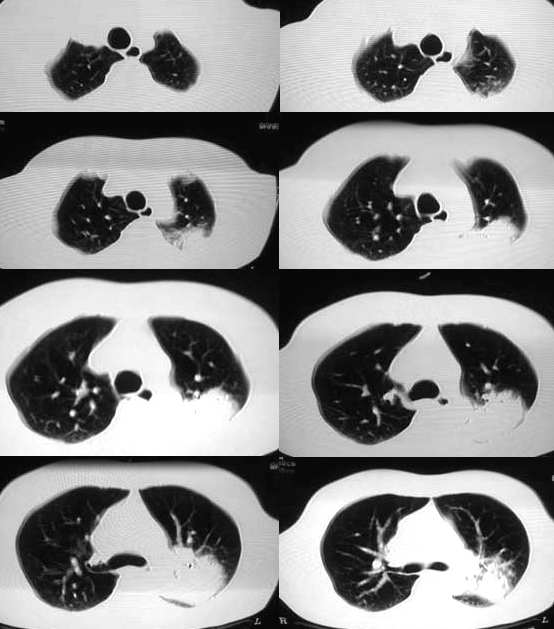

以下是引用ysxyy在2006-3-4 20:19:00的发言:[br]首先考虑炎症,tb暂不考虑;[br]理由:1、病变范围局限在左上肺尖后段,界限较清;[br]2、病史:青壮年34岁,以咳嗽、发热就诊,急性起病;[br]3、

以下是引用lkc8963在2006-3-4 21:27:00的发言:[br][quote]以下是引用ysxyy在2006-3-4 20:19:00的发言:[br]首先考虑炎症,tb暂不考虑;[br]理由:1、病变范围局限在左上肺尖后段,界限较清;[br]2、病史:青壮年34岁,以咳嗽、发热就诊,急性起病;[br]3、